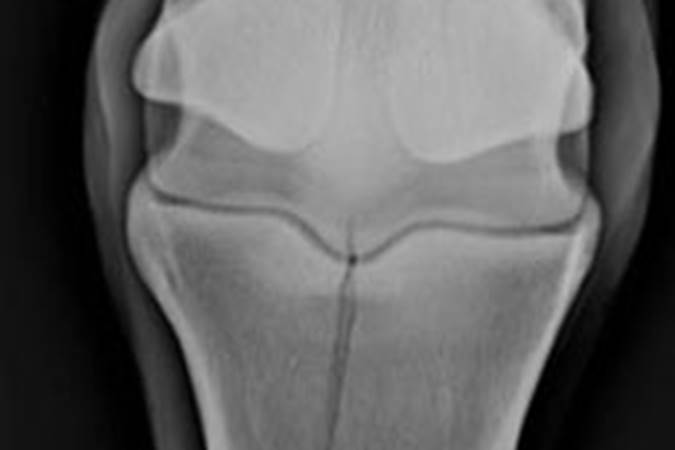

Suspensory desmitis